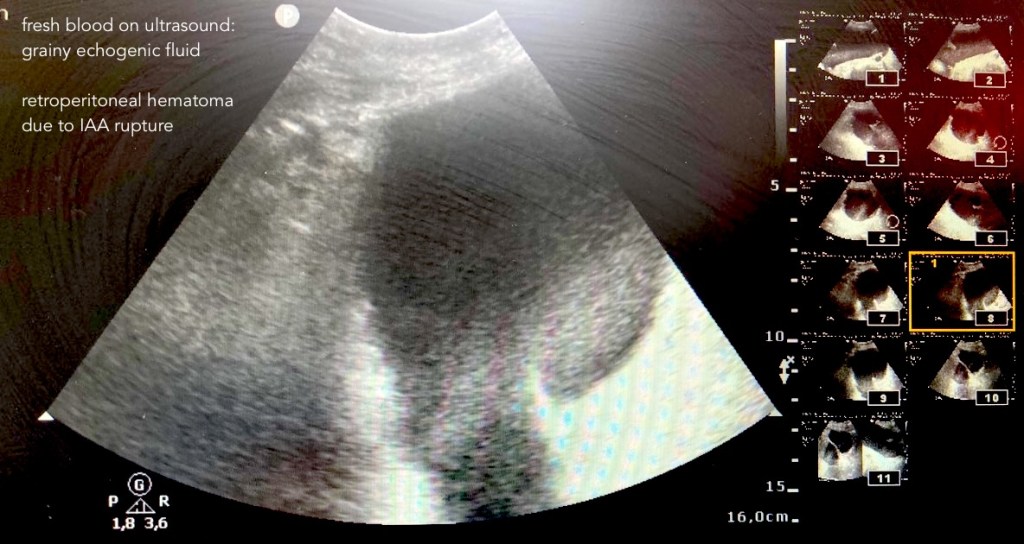

spontaneous retroperitoneal hemorrhage SRH, RPH